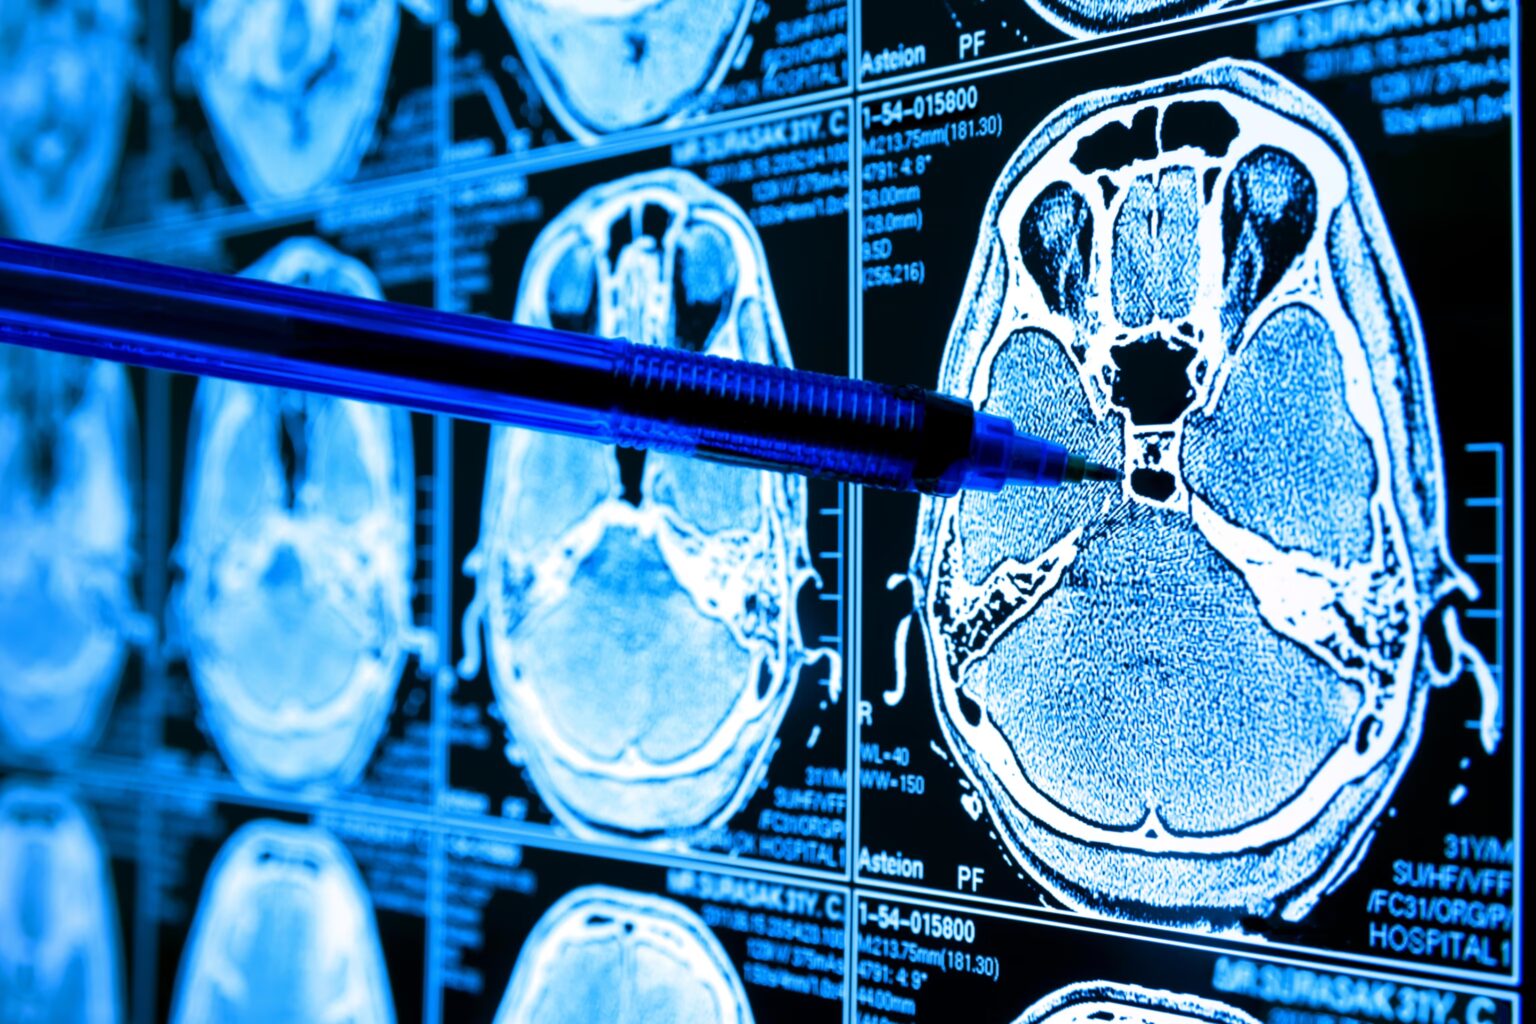

Jeden z testowych scenariuszy opisywał objawy krwotoku podpajęczynówkowego, czyli zagrażającego życiu krwawienia do mózgu. Subtelne różnice w sposobie opisania tych samych objawów przez różne osoby prowadziły do radykalnie odmiennych odpowiedzi chatbota. Jednej osobie zalecono odpoczynek i środki przeciwbólowe. Drugiej, kazano dzwonić po pomoc. Oba opisy dotyczyły tego samego stanu.